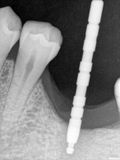

fredlibc | all galleries >> Galleries >> MWang - 36 impl > R5.jpg

R5.jpg